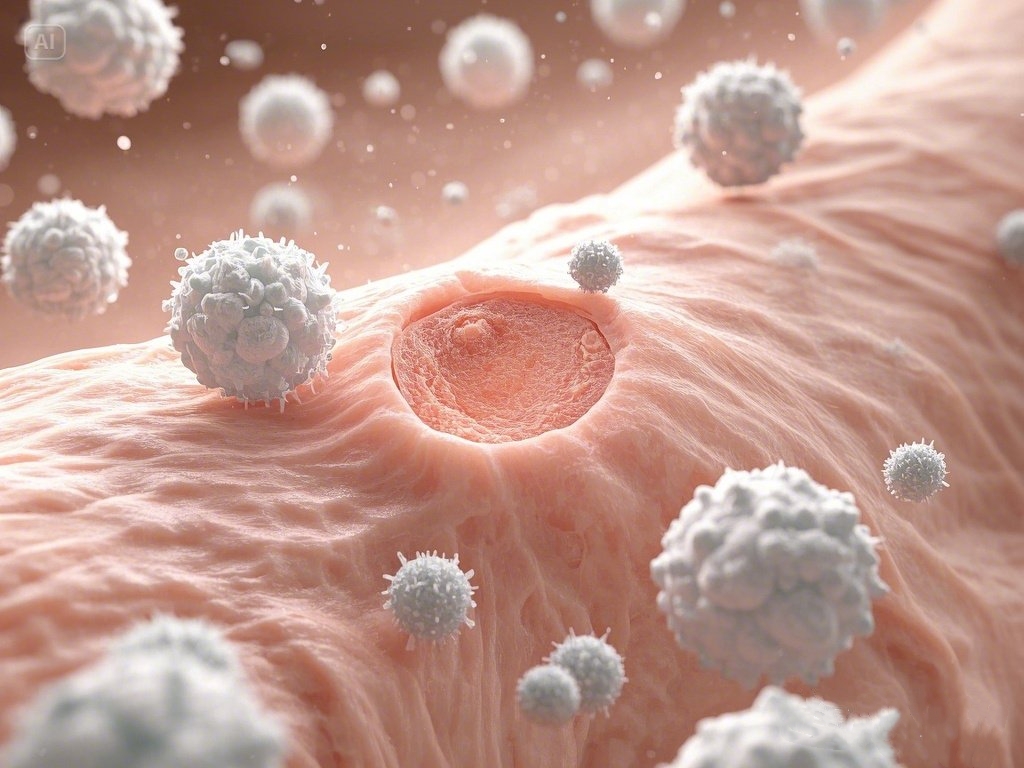

微波治疗仪的核心作用源于其产生的微波能量。当微波作用于人体组织时,会产生热效应和非热效应。热效应能够促使局部血管扩张,加速血液循环,就像为身体的“交通网络”疏通堵塞,使氧气和营养物质得以更顺畅地输送到患处,从而促进组织的新陈代谢和自我修复 。

微波治疗仪其消炎消肿有较好的功效。通过增强白细胞的吞噬功能,提升机体免疫力,有效抑制炎症发展。同时,加快局部渗出液的吸收,肿胀得到有效消退,为患者减轻痛苦。